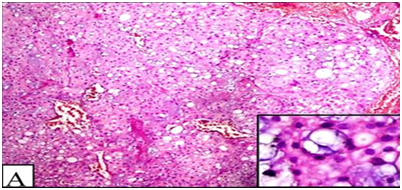

The mass was excised and sent for histopathological examination. Gross examination showed a circumscribed soft tissue mass covered with an elliptical piece of skin with ulceration and sinus formation. Cut surface was firm to hard, vaguely lobulated and variegated with reddish brown hemorrahagic to gelatinous areas (Figure 4). Histopathology revealed a tumour composed of cells arranged in lobulated pattern separated by fibrous septa. The stroma showed myxoid areas and areas of hemorrhage and necrosis. The tumour cells were polyhedral to round with eosinophilic cytoplasm and round atypical nuclei along with physaliphorous cells. Occassional spindle shaped stellate cells and signet ring-like cells were also seen. Physaliphorous cells were large multivacoulated with bubbly appearance of cytoplasm and small inconspicuous nuclei (Figure 5). The cytoplasmic vacuoles were periodic acid Schiff (PAS) positive and diastase sensitive suggesting glycogen deposition (Figure 6). The tumour cells were seen infiltrating the capsule and surrounding soft tissue. The skin overlying tumour showed ulceration and chronic inflammatory cell infiltrate in the dermis. Diagnosis of sacrococcygeal chordoma- NOS was made.

Figure 5 Tumour cells in lobulated pattern with myoid stroma (H&E 100X). Multivacoulated physaliphorous cells (Inset) (H&E 400X).